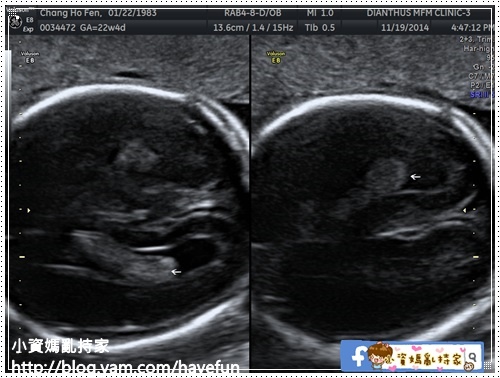

左右兩個眼珠

心臟的四個心房心室

左心室出口

右心室出口

心臟的三條血管

PA肺動脈

AO主動脈

SVC上腔靜脈